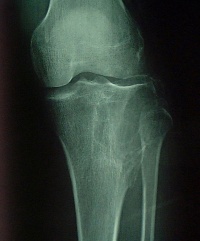

X线平片 对于骨巨细胞瘤的影像学检查, X 线平片是最具诊断价值的放射学检查手段。骨巨细胞瘤在X 线片上表现为骨端的溶骨性破坏,可侵及干骺端,向关节侧延伸侵及部分或全部邻近关节软骨下的骨皮

质。肿瘤大小与发生病变骨的大小有关。肿瘤延患肢骨长轴侵及的范围往往小于延横轴侵及的范围,在骨干侧可见筛孔样改变,而在骨端的周围可见明显的骨皮质膨胀、变薄。病变内部为不同程度的溶骨改变,皮质外多没有骨膜反应;当出现病理骨折时则可见骨膜反应。通常可见到骨膜下新生骨有中断,骨膜保持完整,病变的松质骨边缘部分可有明显的界限。骨巨细胞瘤没有肿瘤基质的矿物化,关节渗出少见,但经常伴有病理性骨折发生。长骨以外部位的骨巨细胞瘤在X 线片上无特征性表现,与其他溶骨病变没有区别。

X线主要表现为骨端变心位溶骨性破坏而无滑膜反应,病灶骨皮质膨胀变薄,呈肥皂泡样改变。

X线片表现:骨骺处有局限的囊性改变,一般呈溶骨性破坏,也可有“肥皂泡”样改变,其扩展一般为软骨所限。不破入关节,少有骨膜反应,肿瘤范围清楚,初发时病变在骨骺内旁侧,发展后可占骨端的全部,骨皮质膨胀变薄,有的可以穿破,进入软组织。X线片可显示其一般特点,但仍不足以确诊。